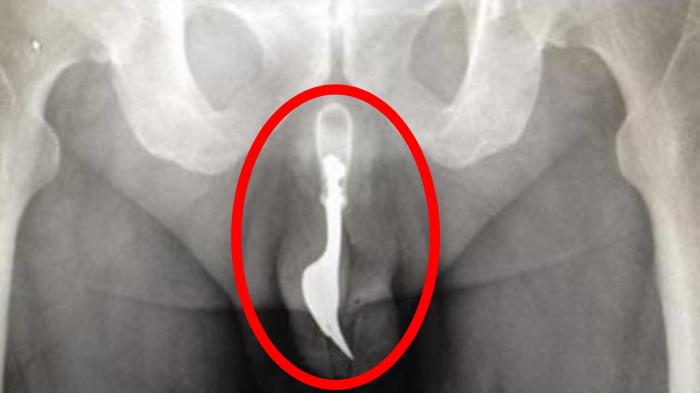

Waspada Saat Berenang, Ikan Ini Suka Masuk ke Alat Kelamin

Bila kamu berenang telanjang, ikan ini akan masuk melalui celah anus atau vagina, bahkan bila ukurannya sangat kecil bisa masuk ke lubang penis.

Yang mengejutkan, ikan candiru bisa masuk ke tubuh manusia melalui alat kelamin laki-laki yang suka pipis sembarangan di sungai. Kabar baiknya, ikan ini tidak dijumpai di Indonesia.

Candiru merupakan ikan yang berada dalam ordo ikan lele (Siluriformes), tetapi ukurannya jauh lebih kecil daripada lele yang biasa kita jumpai.

Ukuran terbesar dari ikan candiru hanya sepanjang 15 cm, tapi rata-rata hanya memiliki panjang tubuh 5 cm.

Bila hal itu terjadi, maka akan sangat sulit sekali mengeluarkannya kecuali dengan operasi.